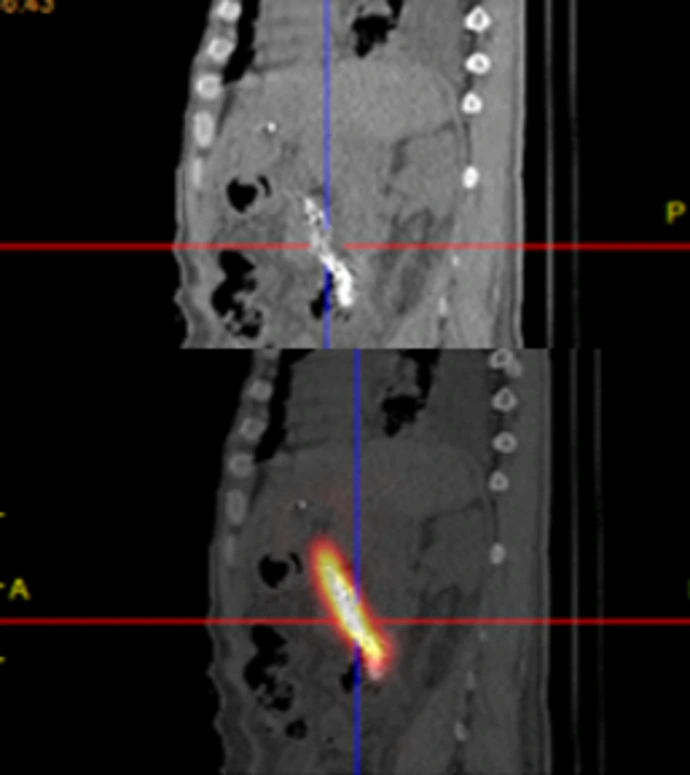

胆道粒子支架是将金属胆道支架与放射性粒子(通常为碘-125,¹²⁵I)相结合的一种创新型介入治疗手段。

持续内照射作用

支架上均匀分布的¹²⁵I放射性粒子可持续释放低能量γ射线,可在局部形成持续数月的放射治疗效应,抑制肿瘤细胞增殖、诱导肿瘤细胞凋亡。

粒子支架长期保障胆管通畅

粒子导管来救场

将“减黄”(引流)和“抗肿瘤”(粒子)两种治疗合二为一。通常采用三腔结构,包括一个较大的胆汁引流腔和一到两个较小的粒子腔。

将携带粒子的引流管引入狭窄支架内

粒子能量在支架内局部释放,引流的同时,使支架再通